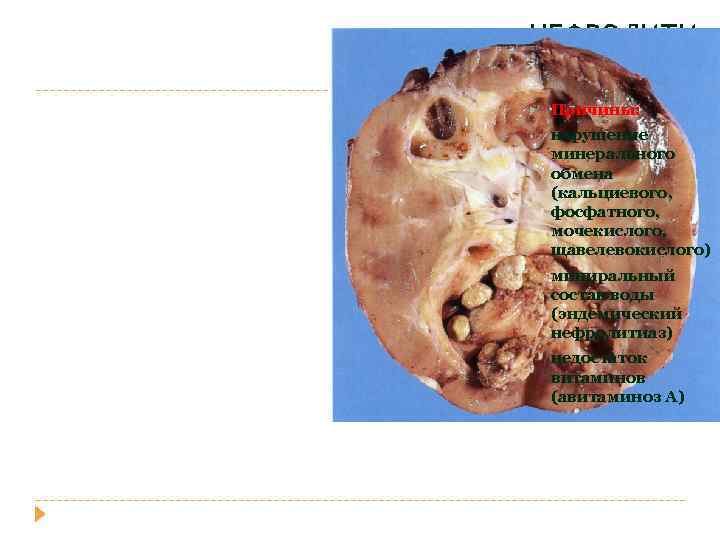

НЕФРОЛИТИ АЗ Причины: • нарушение минерального обмена (кальциевого, фосфатного, мочекислого, щавелевокислого) • миниральный состав воды (эндемический нефролитиаз) • недостаток витаминов (авитаминоз А)

оксалаты и ураты (80%) • рентгенопозитивные камни • при увелечении абсорбции кальция в тонкой кишке аммониевомагниевые соли • коралловые, рентгенонегативные фосфорной • при щелочной реакции мочи кислоты ураты цистиновые камни • гиперурикемии

обструкция пилоэктазия (расширение лоханки) гидронефроз + пиелонефрит, хронический паранефрит панцерный паранефрит, ХПН пионефроз, сепсис, уремия